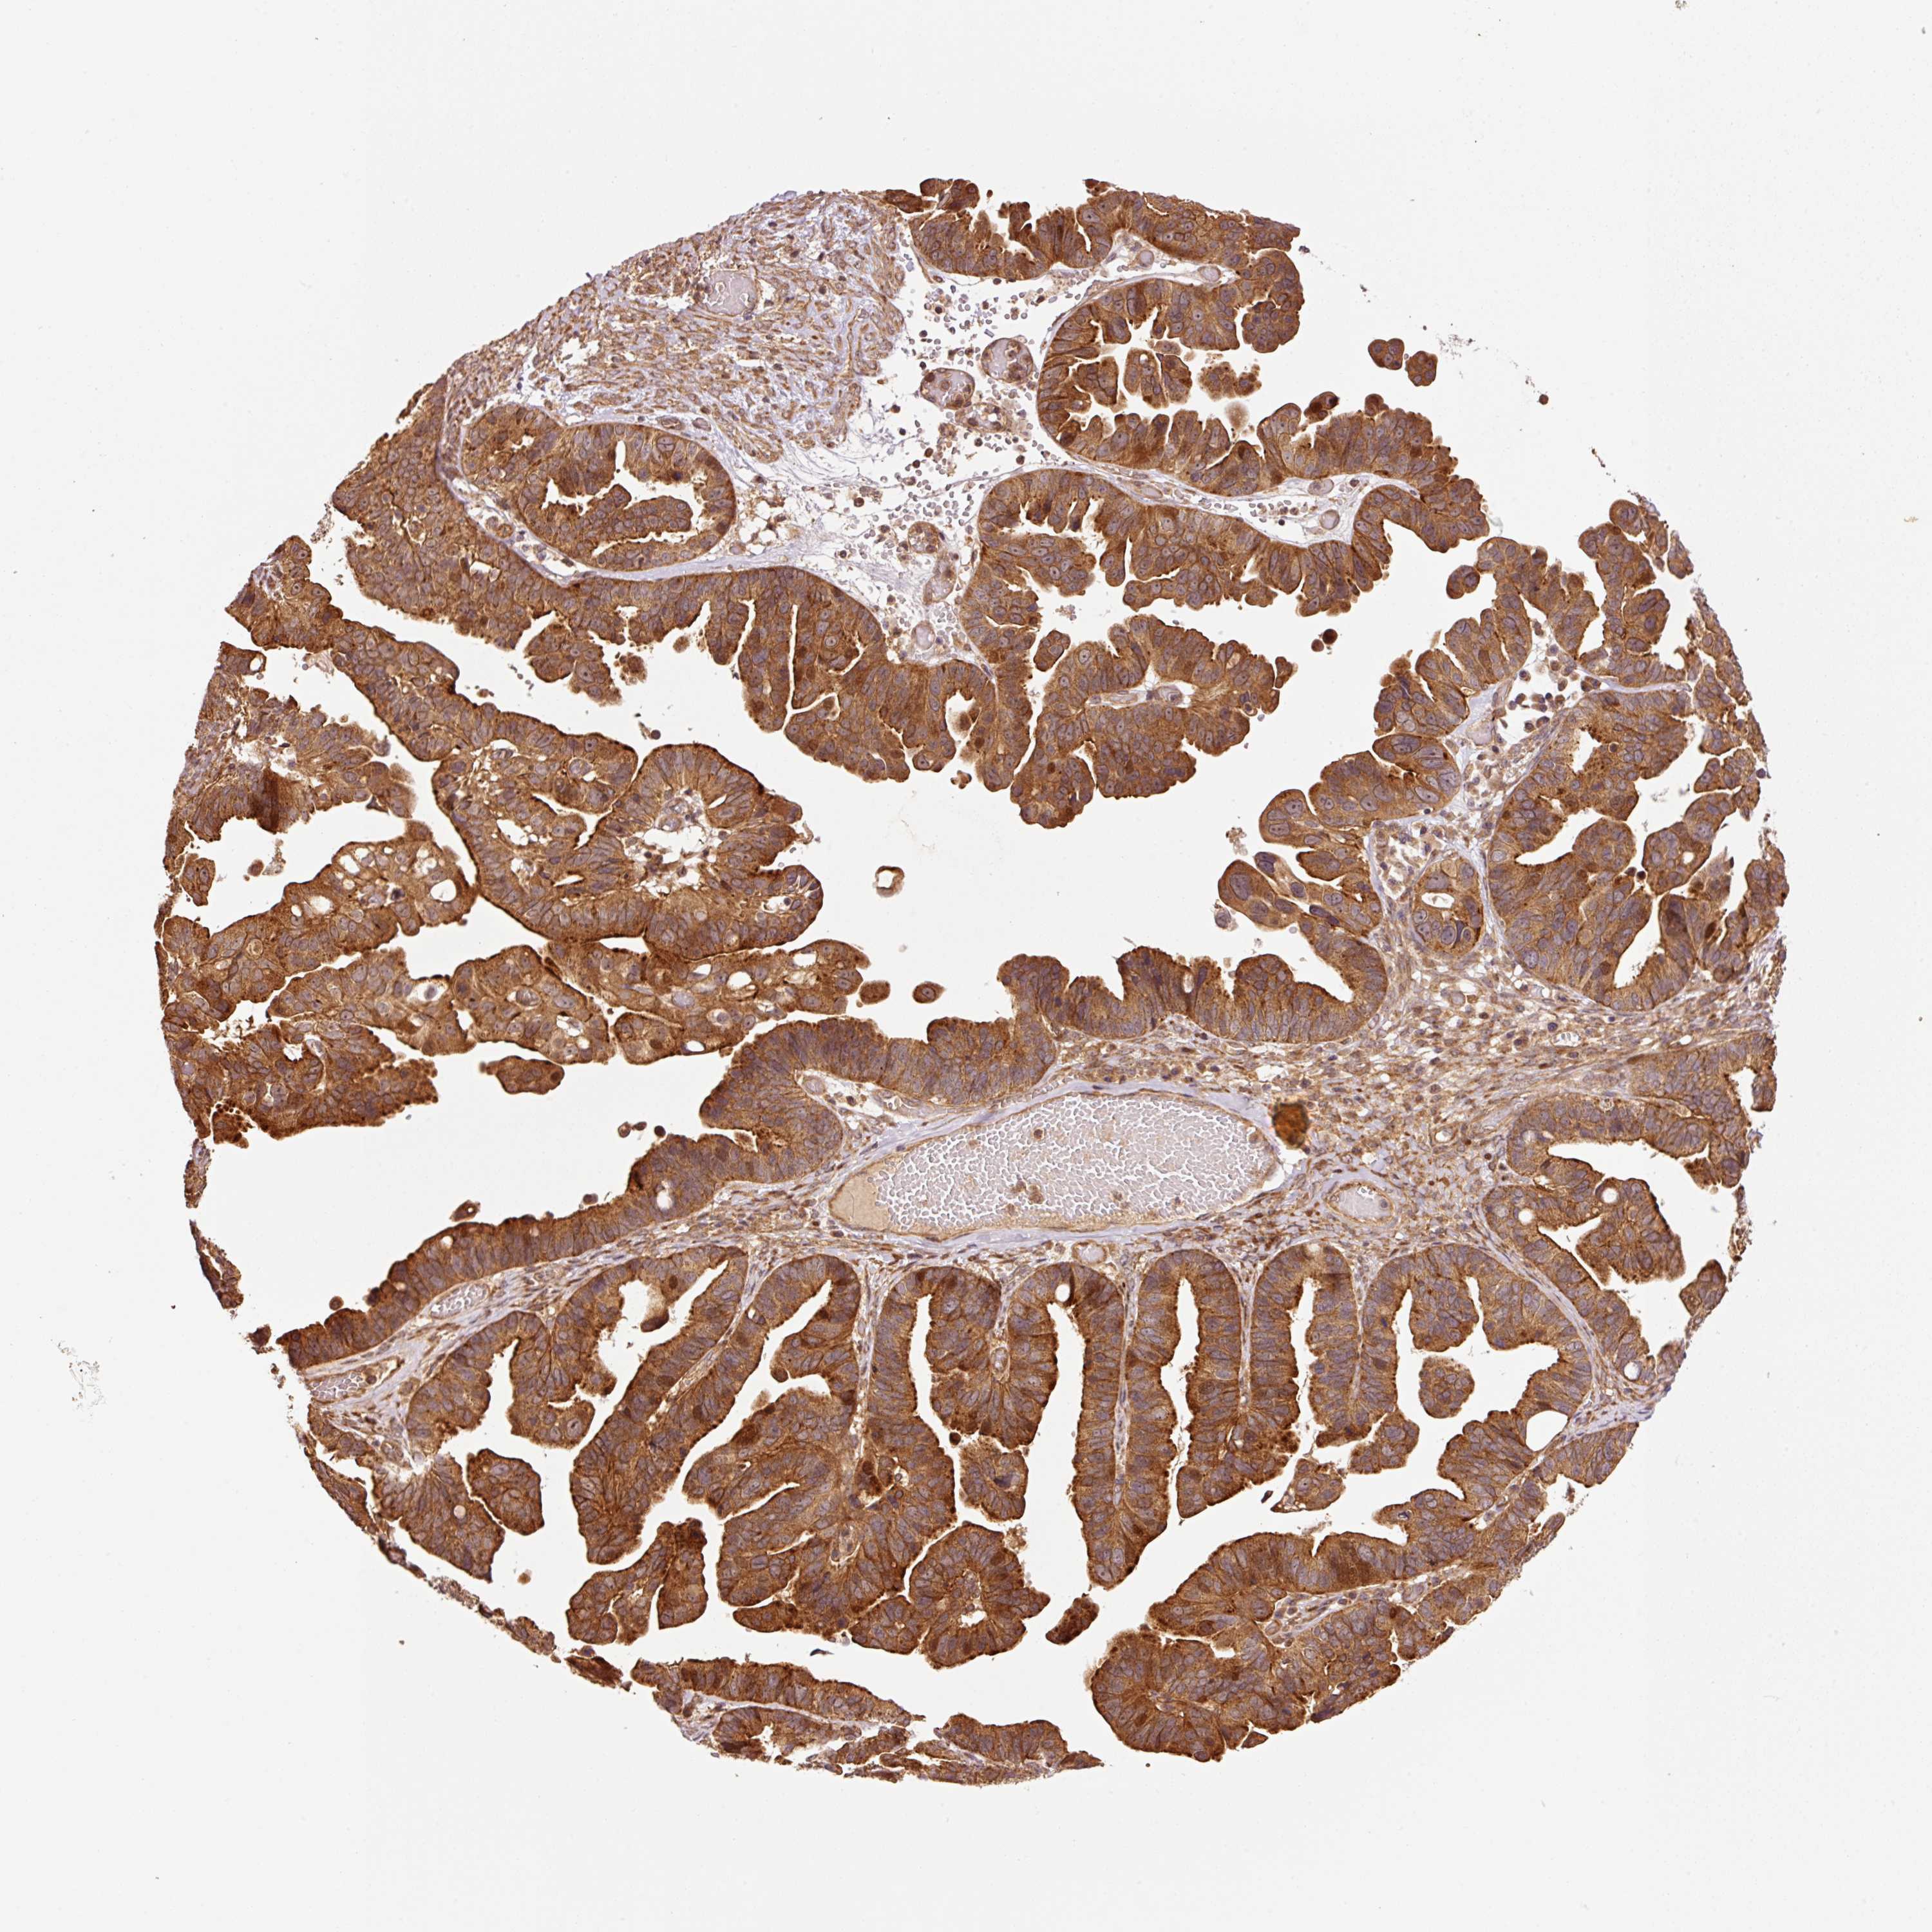

OVARIAN CANCER - Protein expressioni

A mouse-over function shows sample information and annotation data. Click on an image to view it in a full screen mode. Samples can be filtered based on level of antibody staining by selecting one or several of the following categories: high, medium, low and not detected. The assay and annotation is described here.

Note that samples used for immunohistochemistry by the Human Protein Atlas do not correspond to samples in the TCGA dataset.

Antibody stainingi

Antibody staining in the annotated cell types in the current human tissue is reported as not detected, low, medium, or high, based on conventional immunohistochemistry profiling in selected tissues. This score is based on the combination of the staining intensity and fraction of stained cells.

Each image is clickable and will lead to virtual microscopy that enables deeper exploration of all samples and also displays staining intensity scores, fraction scores and subcellular localization as well as patient and tissue information for each sample.

Antibody HPA051433

Staining

High

Medium

Low

Not detected

Intensity

Strong

Moderate

Weak

Negative

Quantity

>75%

75%-25%

<25%

None

Location

Nuclear

Cytoplasmic/membranous

Cytoplasmic/membranous,nuclear

Cystadenocarcinoma, serous, NOS

Carcinoma, endometroid

Cystadenocarcinoma, mucinous, NOS

Carcinoma, NOS